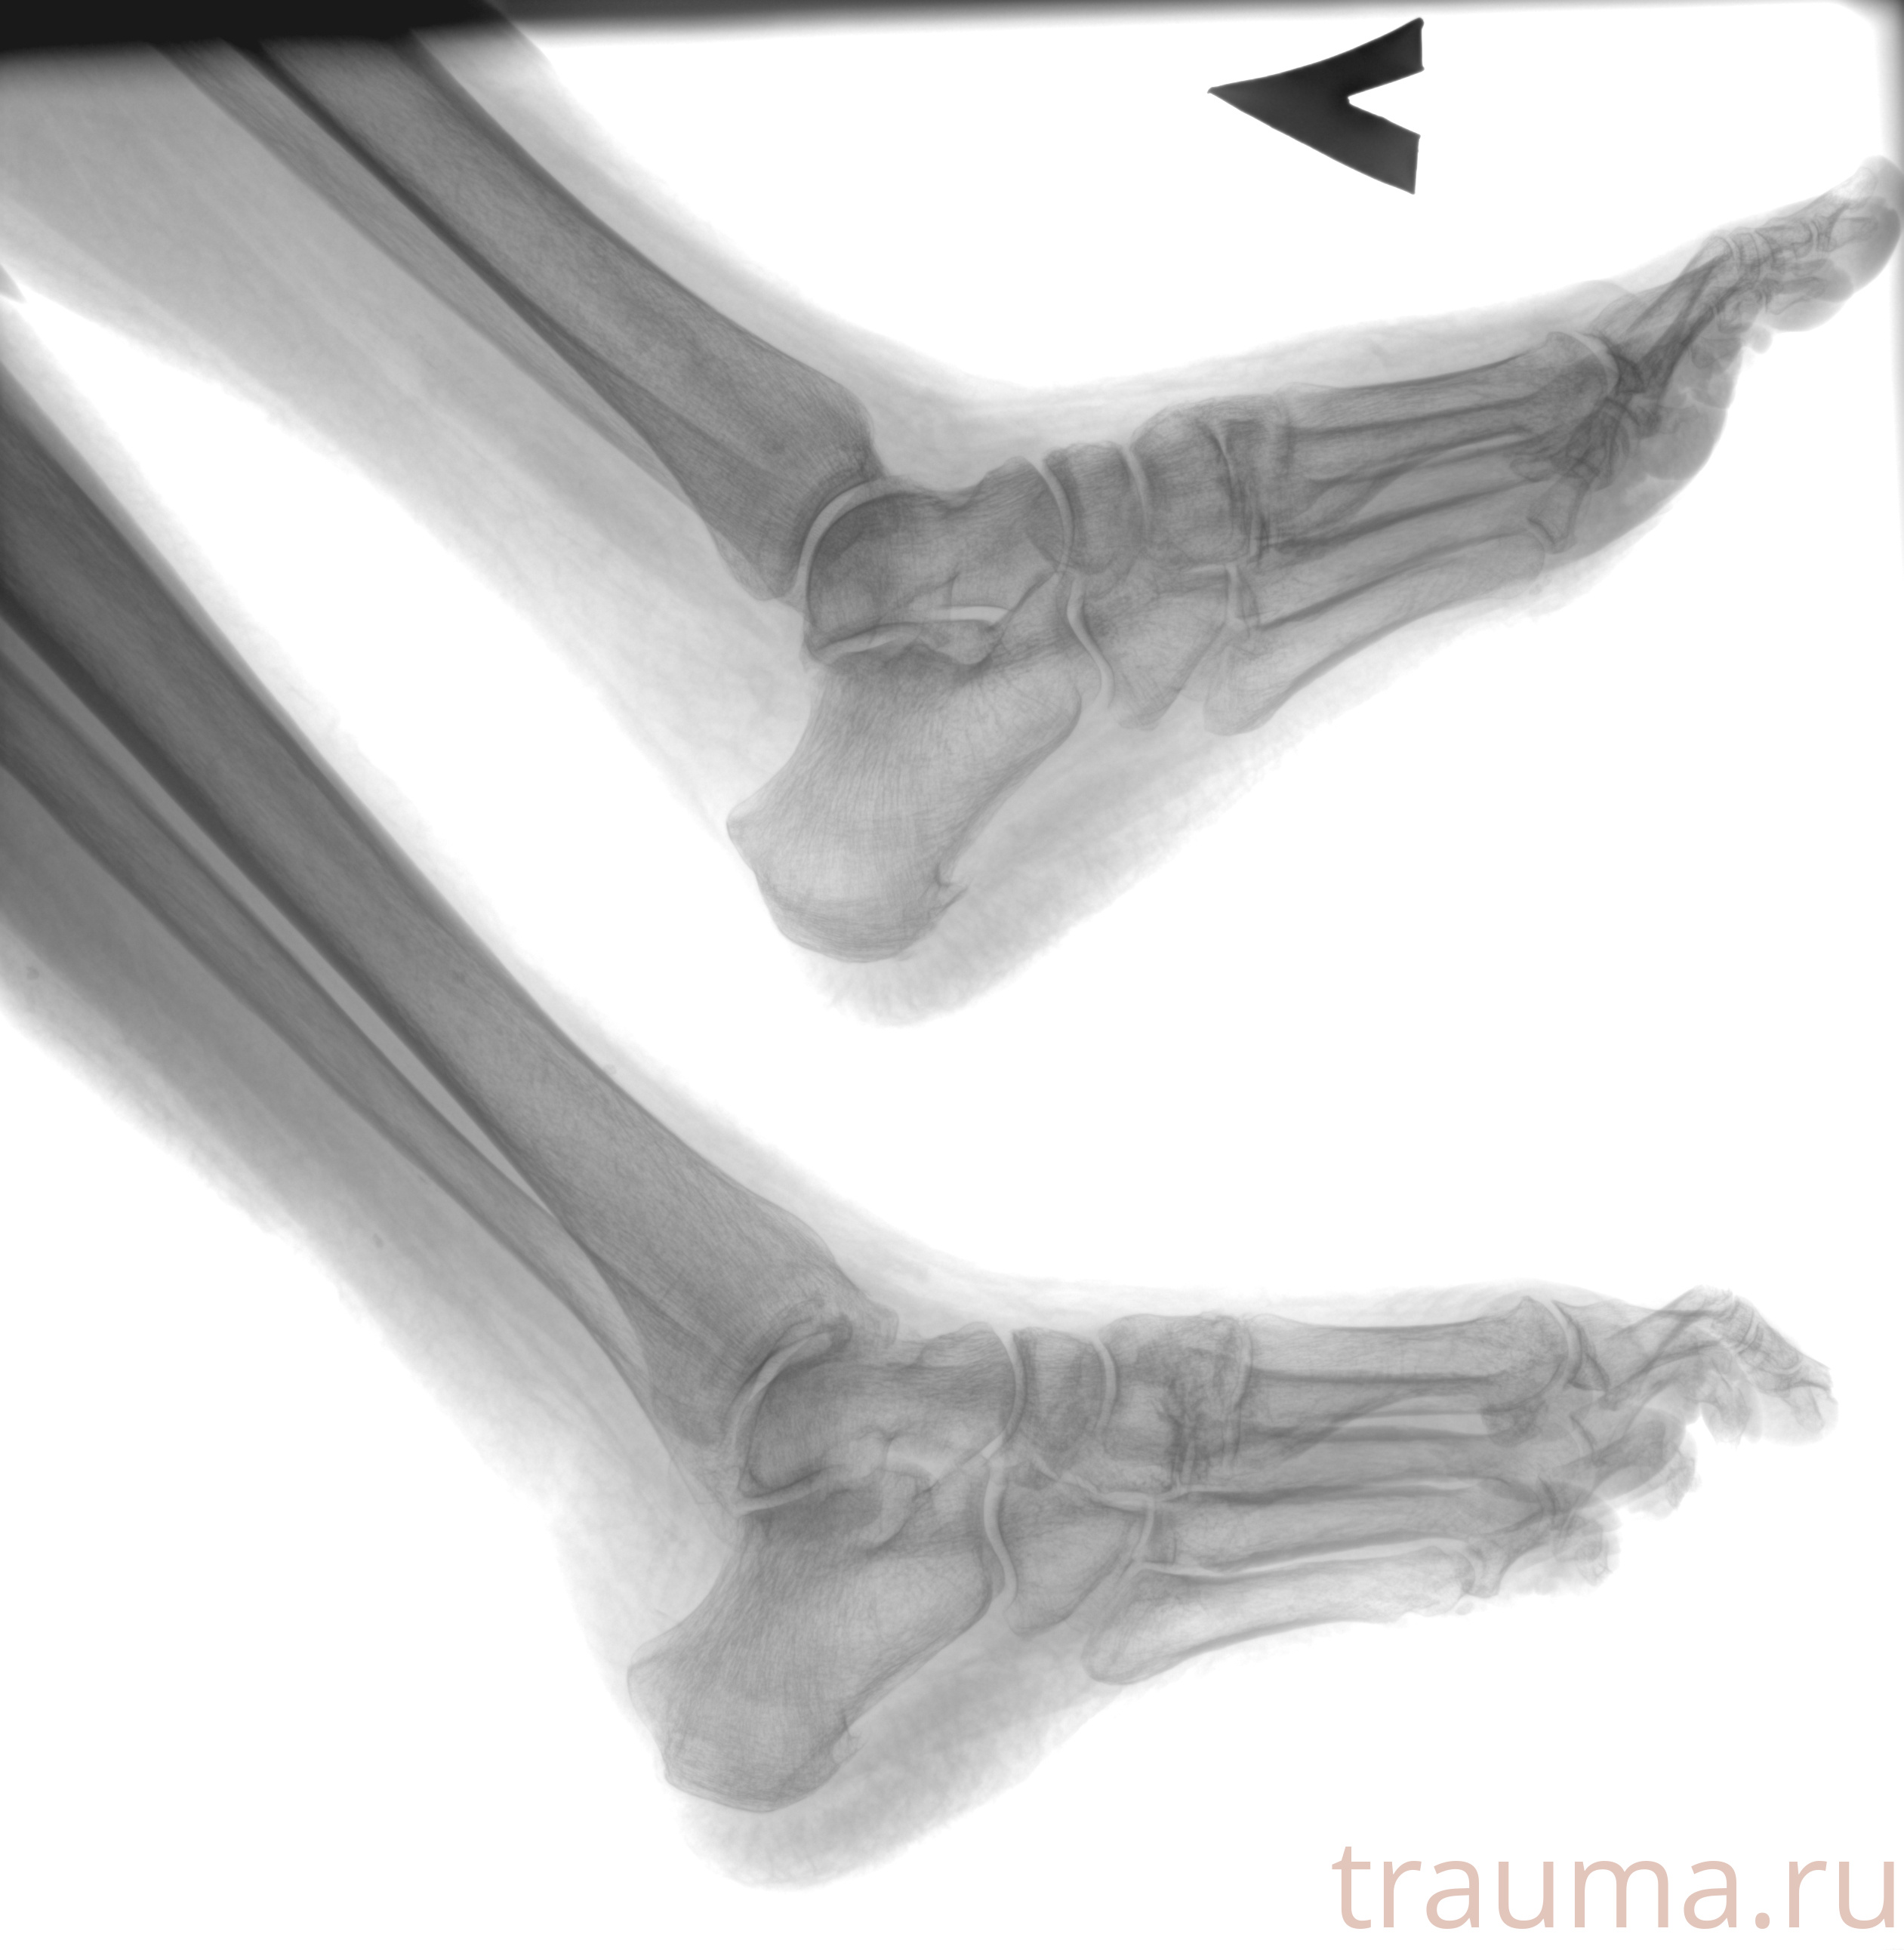

Рентген на дому: по вашему адресу приезжает врач-рентгенолог, травматолог-ортопед с мобильным рентгеновским аппаратом, проводит диагностику травмы или заболевания, делает необходимые рентгенограммы, дает рекомендации по дальнейшему лечению. Получить качественные снимки в домашних условиях возможно благодаря уникальной методике, разработанной МосРентген Центром для института  Склифосовского